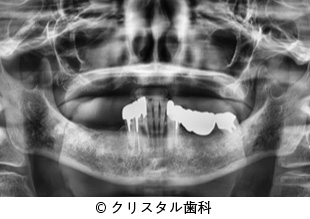

【症例2】崩壊した臼歯部にインプラント治療、上顎前突を矯正治療した症例

- 崩壊した臼歯部にインプラント治療、上顎前突を矯正治療した症例

- 3,208,000円(税込)

- 2年3ヵ月

患者様の症状

歯周病で骨が無くなった奥歯に強い痛みを感じており、インプラント治療を希望された。

また、前歯が出っ歯であり、同時に矯正治療で審美的な改善を希望された。 -

治療法

歯周病で歯の周りの骨を失った歯は抜歯して骨を再生し、インプラントを埋入した。

前歯の前突は全顎矯正にて審美的に改善した。その後、インプラントにはセラミックスを被せることでよく噛める状態を確立した。 -

治療結果

インプラントにセラミックスを被せることで、よく噛めるようになり、矯正治療によって前歯の前突も改善したことで、患者様からはよく噛めて綺麗になったと高い満足感の感想をいただいた。

治療を行う上での 注意点 (リスク・副作用)

出血、疼痛、インプラント周囲炎。